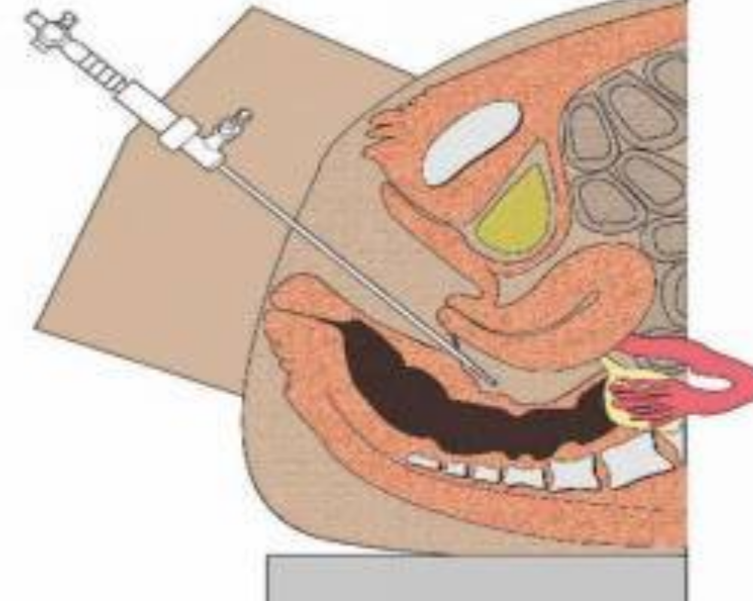

人工陰道治療中的

人工陰道作用

人工陰道治療

A:原發性陰道鱗狀上皮癌對放療比較敏感,可採用腔內鐳療、體外照射或放射性同位素局部應用等治療。一般早期陰道癌以腔內照射為主,放射源主要為鐳及鈷,現在多用銫,利用陰道容器,裝配不同劑量及放置不同時間。體外照射治療時放射量由主治醫師根據患者情況具體……